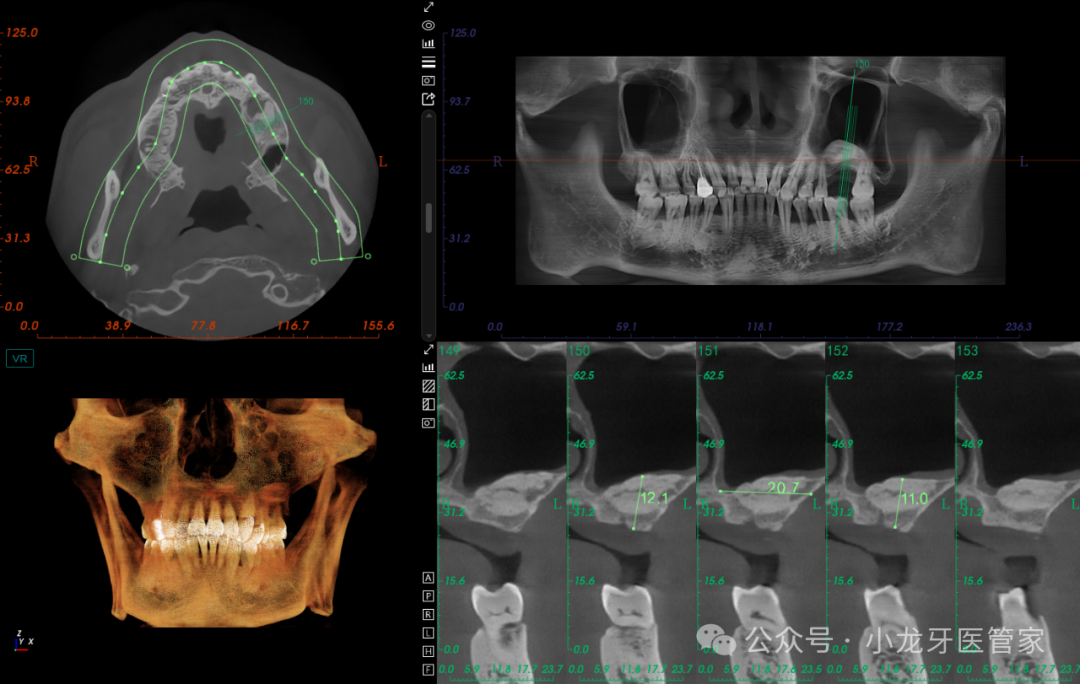

种植一期手术:

患者知情同意并签署《口腔种植修复知情同意书》。常规消毒铺巾,4%阿替卡因局部浸润麻醉,26缺牙区牙槽嵴顶作水平切口,全层切开粘骨膜,翻瓣,发现缺牙区骨面平坦,整体骨质较硬(III类骨),定位,先锋钻备洞至预定深度,扩孔钻逐级扩孔,制备种植体窝,置入ITIblt骨水平种植体,型号:4.8mm*10 mm,植入扭矩35N.cm,旋入覆盖螺丝。减张缝合。

术后影像学图片